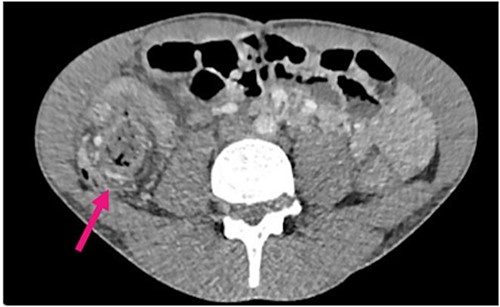

Radiological investigations included a contrast computerized-tomography (CT) of the abdomen/pelvis and suggestive of intussusception of the caecum into the ascending colon, with a thickened appendix. Due to the presence of faecal loading, it was not clear radiologically whether the combined clinical picture was suggestive of distal intestinal syndrome (Figs 1 and 2) due to faecal loading only, or true intussusception of the appendix.

Contrast CT coronal sections depicting the classical ‘bullseye sign’ of intussusception of the caecum into the ascending colon.